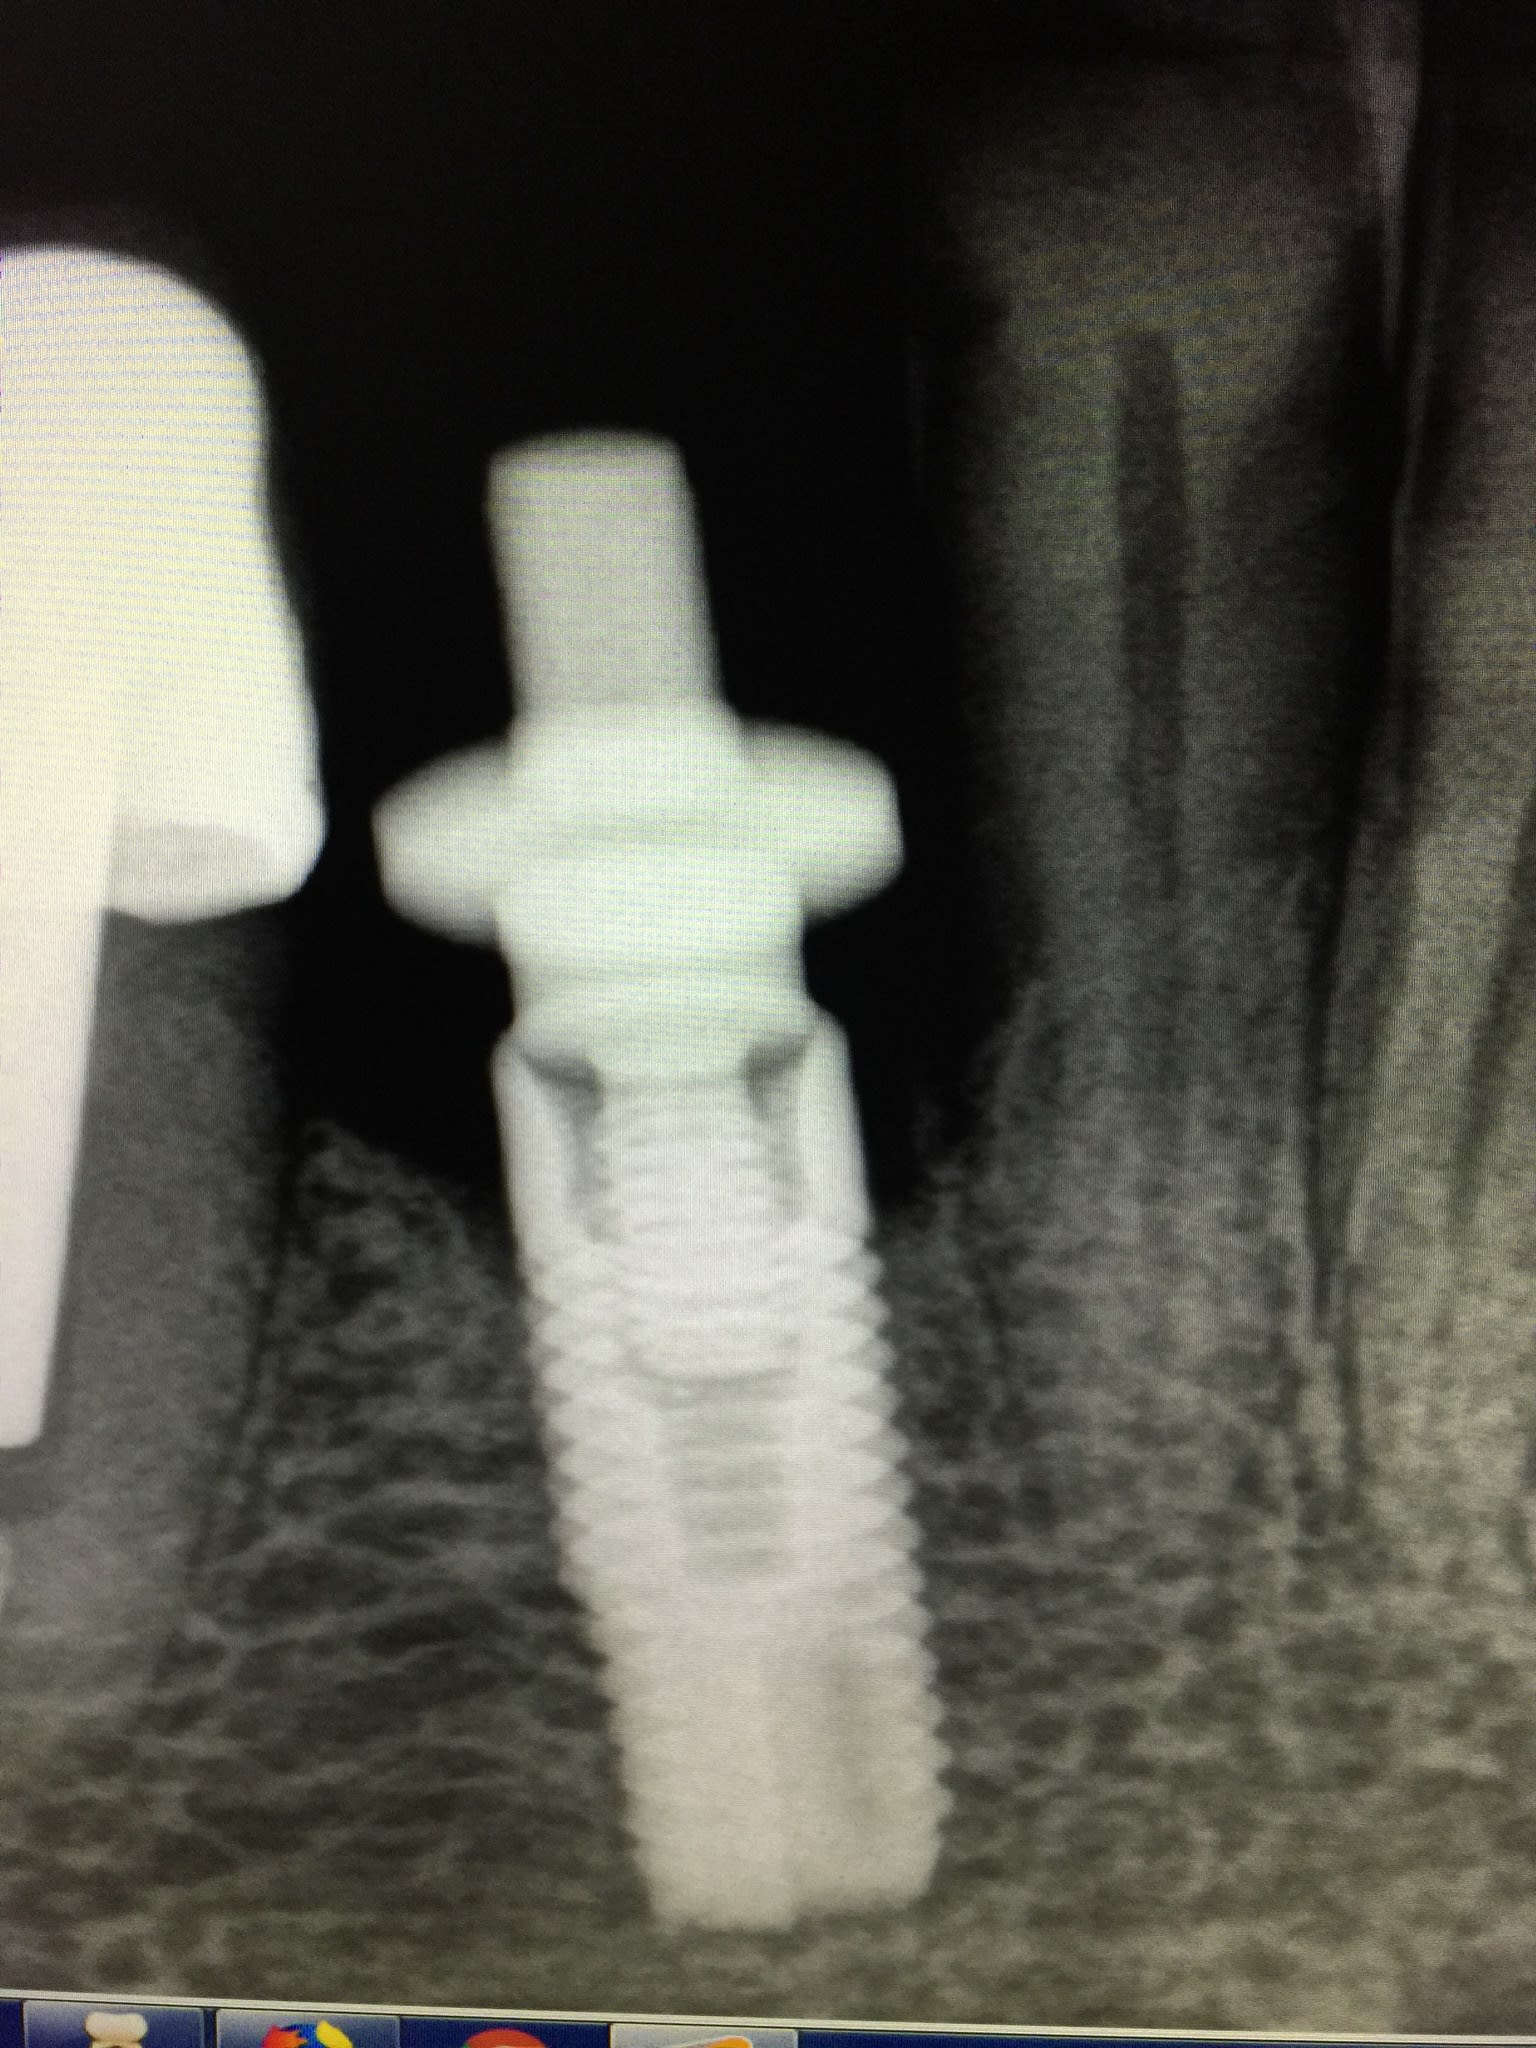

Une patiente a sa prothèse implantaire qui se dévisse.

Le successeur de son ancien practicien m'a communiqué la référence de son implant(astra 3,5).

Mais a la radio,cela ne me semble pas un astra.

De plus,j'avais une pièce prothétique compatible astra,mais ça ne rentre pas.

Quelqu'un pour m'aider à l'identifier ?

pas top tes radios....

j'ai un peu de mal à définir vraiment la connexion...

du coup difficile d'avoir un avis fiable...

Bonjour, selon vos radios c'est Astra 4.0

Visitez cette page pour avoir plus de détails :http://www.dentsplyimplants.com/en/Implant-systems/ASTRA-TECH-Implant-System-catalog

heu..., si et seulement si il y a des microspires au col...or avec la qualité des images fournies...j'ai beau grossir les images...j'vois rien de çà...

et sincèrement, vu l'angle de prise de cliché, j'ai aussi un doute sur la pente de la connexion...c'est peut être même tout simplement un classique hex "Zimmer"....et non un cône astra...

bref: une bonne rétro bien positionnée, sans l'étage prothétique, voir pourquoi pas une photo en plus de la connexion et on aura tous les éléments...